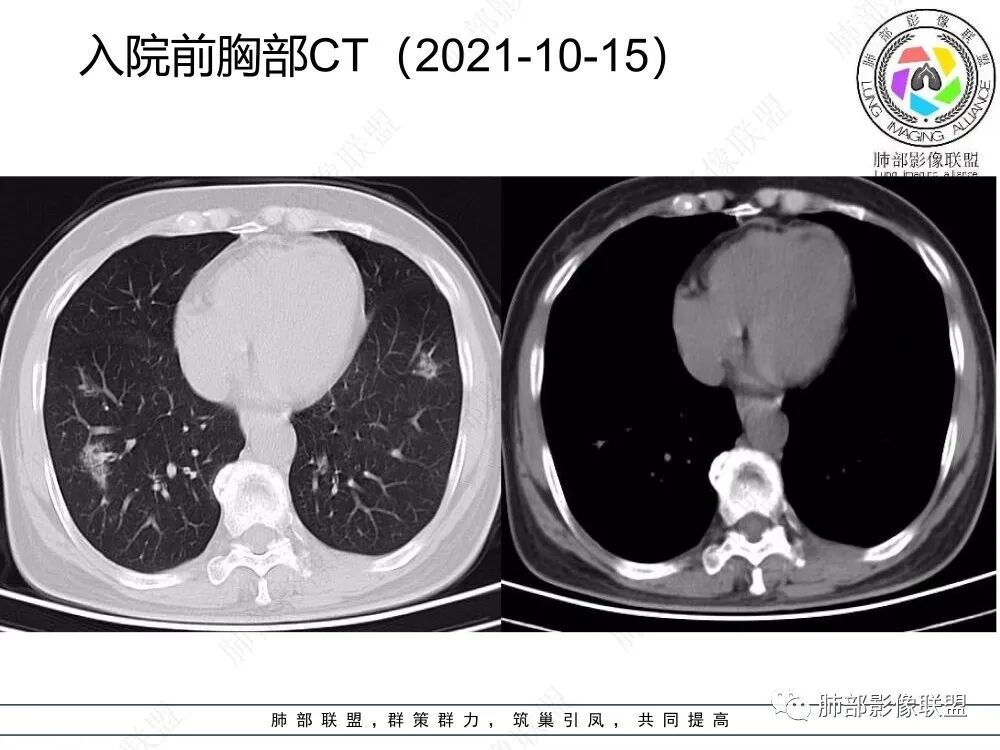

2、CT表现为两肺下叶结节影、斑片影、磨玻璃影,沿支气管血管束分布,部分支气管壁显示增厚。粗略一看部分病灶内似可见“细网格影”,但是仔细观察,可发现此“细网格影”不同于我们常见的“细网格影”,尤其是右肺下叶病灶,可以观察到病灶内部的网格上有高密度结节感或颗粒感,部分层面见“反晕征”,且反晕的边缘亦可观察到结节感。未见胸腔积液。

3、反晕征又称为环礁征、环岛征或环状珊瑚岛征,表现为中心磨玻璃影,周围为高密度影环绕,最初被认为是隐源性机化性肺炎(COP)的特征性表现之一,但随后不断有研究发现反晕征亦可出现在多种感染及非感染性疾病、肿瘤及非肿瘤性疾病中。反晕征的常见疾病谱有:①感染性疾病:肺孢子菌病、侵袭性肺真菌感染、肺结核、病毒性肺炎;②非感染性疾病:肺淋巴瘤样肉芽肿、韦格氏肉芽肿、 结节病、机化性肺炎(包括隐源性和继发性)、肺栓塞;③肺腺癌以及肺肿瘤治疗后。

4、本例急性病程,发热、咳嗽,结合影像多发磨玻璃影表现首先会考虑到感染性病变:①病毒性肺炎,病灶间质分布为主,常较弥漫,外围多见,临床症状重且常与影像表现同步;②支原体肺炎,病变多为1-2叶段、少数多叶段分布,支气管壁弥漫较均匀增厚,可见树芽征、腺泡结节及树雾征;③肺结核,上叶尖后段及下叶背段多见,多灶性、多态性,树芽征,可有空洞、钙化等;④机化性肺炎,病变胸膜下和支气管血管束分布,可有实变、结节及反晕征。

本例病变以两肺下叶为主,非结核好发部位,通常会想到感染性病变,右肺下叶病灶高密度结节感、反晕征,较为符合继发性肺结核(间质浸润为主),但双肺散落的相对柔和淡薄小片影给诊断带来困惑。